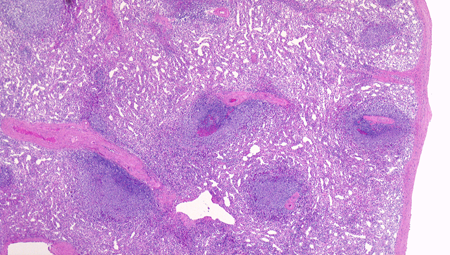

脾臓の構造, 組織所見

脾臓の割面を肉眼で見ると暗赤色の赤脾髄中に白色点状の白脾髄が散在している

赤脾髄は脾洞と脾索から構成され赤血球を多く含む。白脾髄はリンパ小節でリンパ球の集蔟巣である。

白脾髄の構造

白脾髄, 辺縁帯/周辺帯は脾臓のリンパ装置として機能する. 開放性末梢血管流床を介して伝達される免疫情報はこれらのリンパ装置で処理され効率よく免疫反応がおこる.

白脾髄 white pulpは中心動脈周囲に形成されているリンパ組織で, 動脈周囲リンパ鞘 periarteriolar lymphoid sheath(PALS)とリンパ濾胞(lymph follicles)の異なる2つの領域が識別される.

辺縁帯/周辺帯 Marginal zone

辺縁帯 Marginal zone*14

脾臓の辺縁帯は通常,よく発達した濾胞周囲領域であり,そろった/一様な核と一定量の透明な細胞質を持つ中型のリンパ球からなり,芽球が散在している。